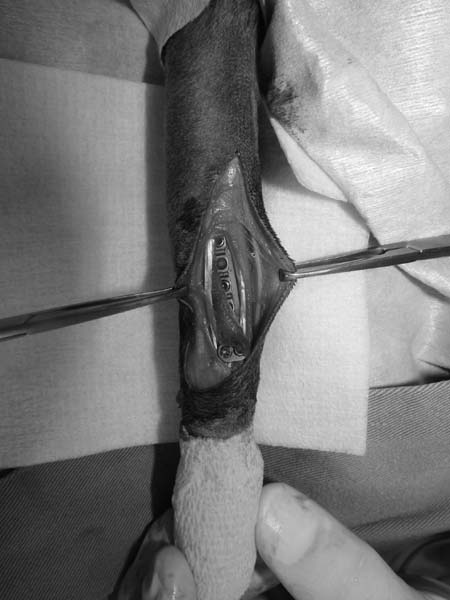

5~6歳以上の去勢手術をしていないオス犬に多い病気ですが、メス犬や去勢した犬に起こることもあります。お尻の筋肉が萎縮した結果、筋肉の隙間から直腸や膀胱が皮膚の下にとびでてしまいます。これにより便が出にくくなったり膀胱炎になったりします。手術をすることで機能回復および今後の致死的な状況を回避することができます。当院では去勢手術→結腸固定→前立腺固定→骨盤隔膜構成筋の縫縮→内閉鎖筋フラップ→浅臀筋フラップの順で通常腹側・臀部左右両側同時に行います。また老化以外に、筋肉が萎縮する原因があったり、腹圧がかかる原因があったりする場合も多いので、再発防止のためそれらの診断・治療も重要です。今回のワンちゃんも無事手術も終わり元気に退院しました。よかったね。